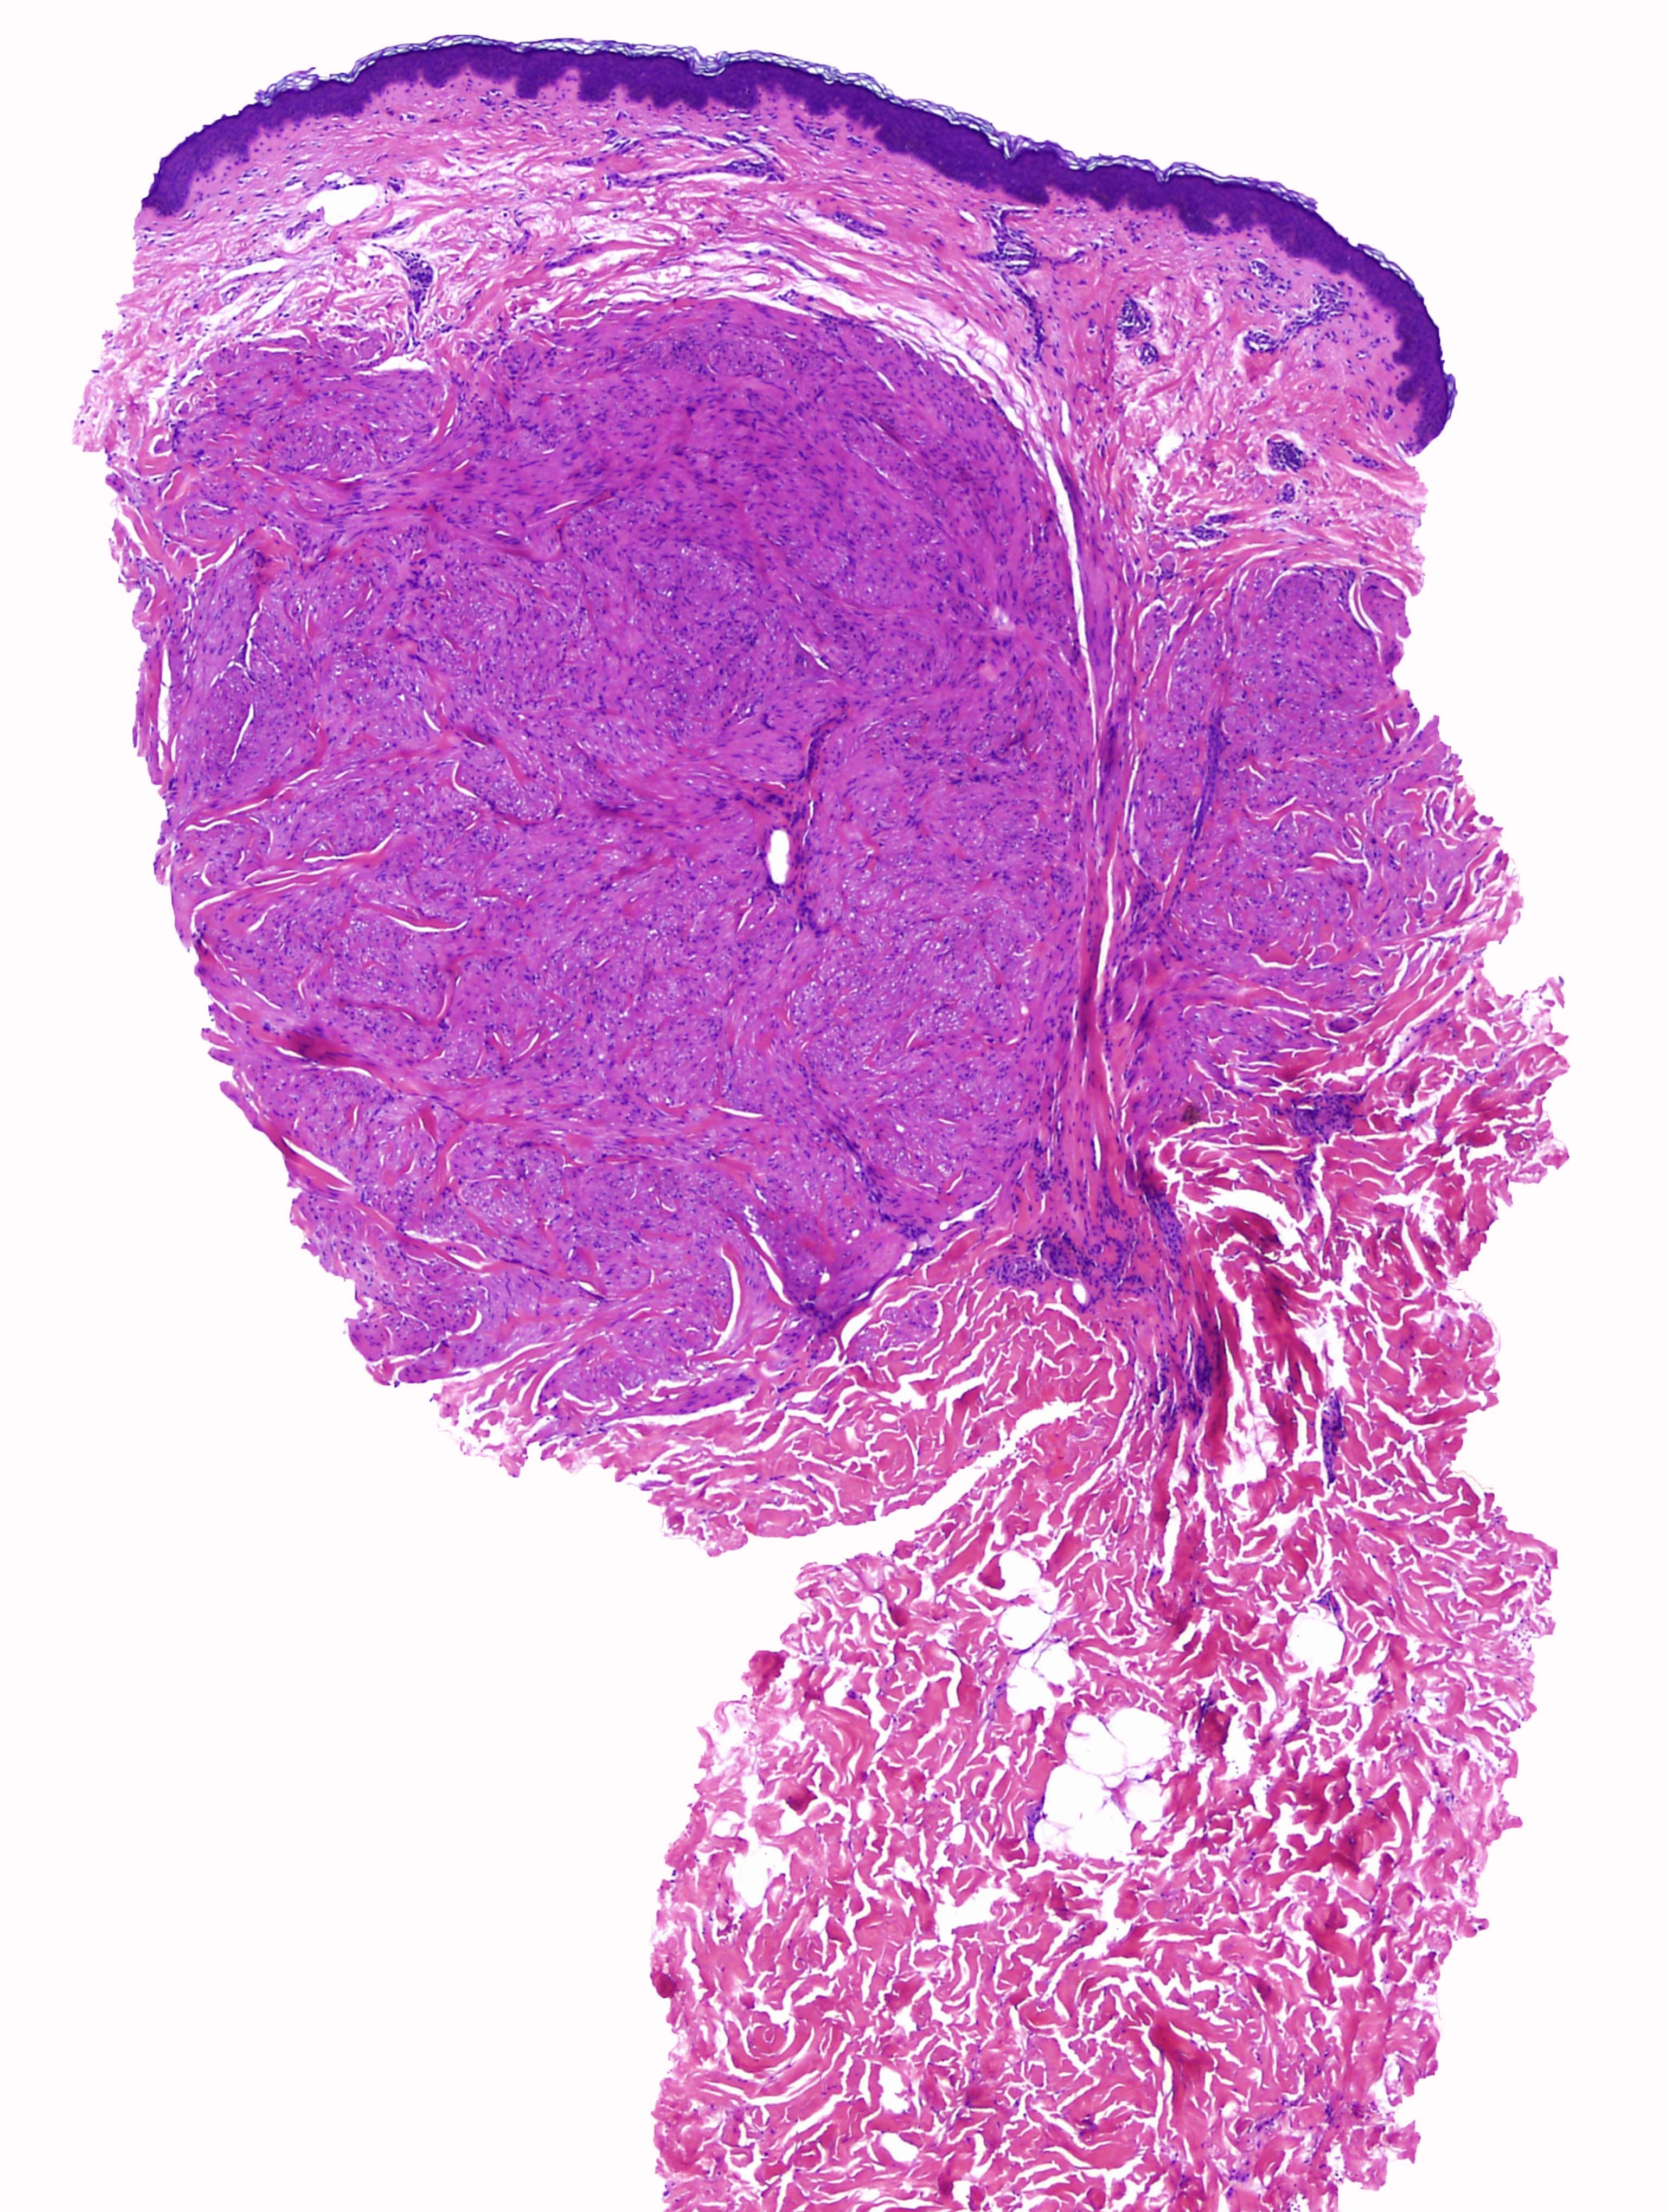

Cas dermatopatologia. Un cas adequat per a aquesta estació de l'any

Gener 2013

Podria suggerir-se el diagnòstic sense conèixer l'historial clínic?